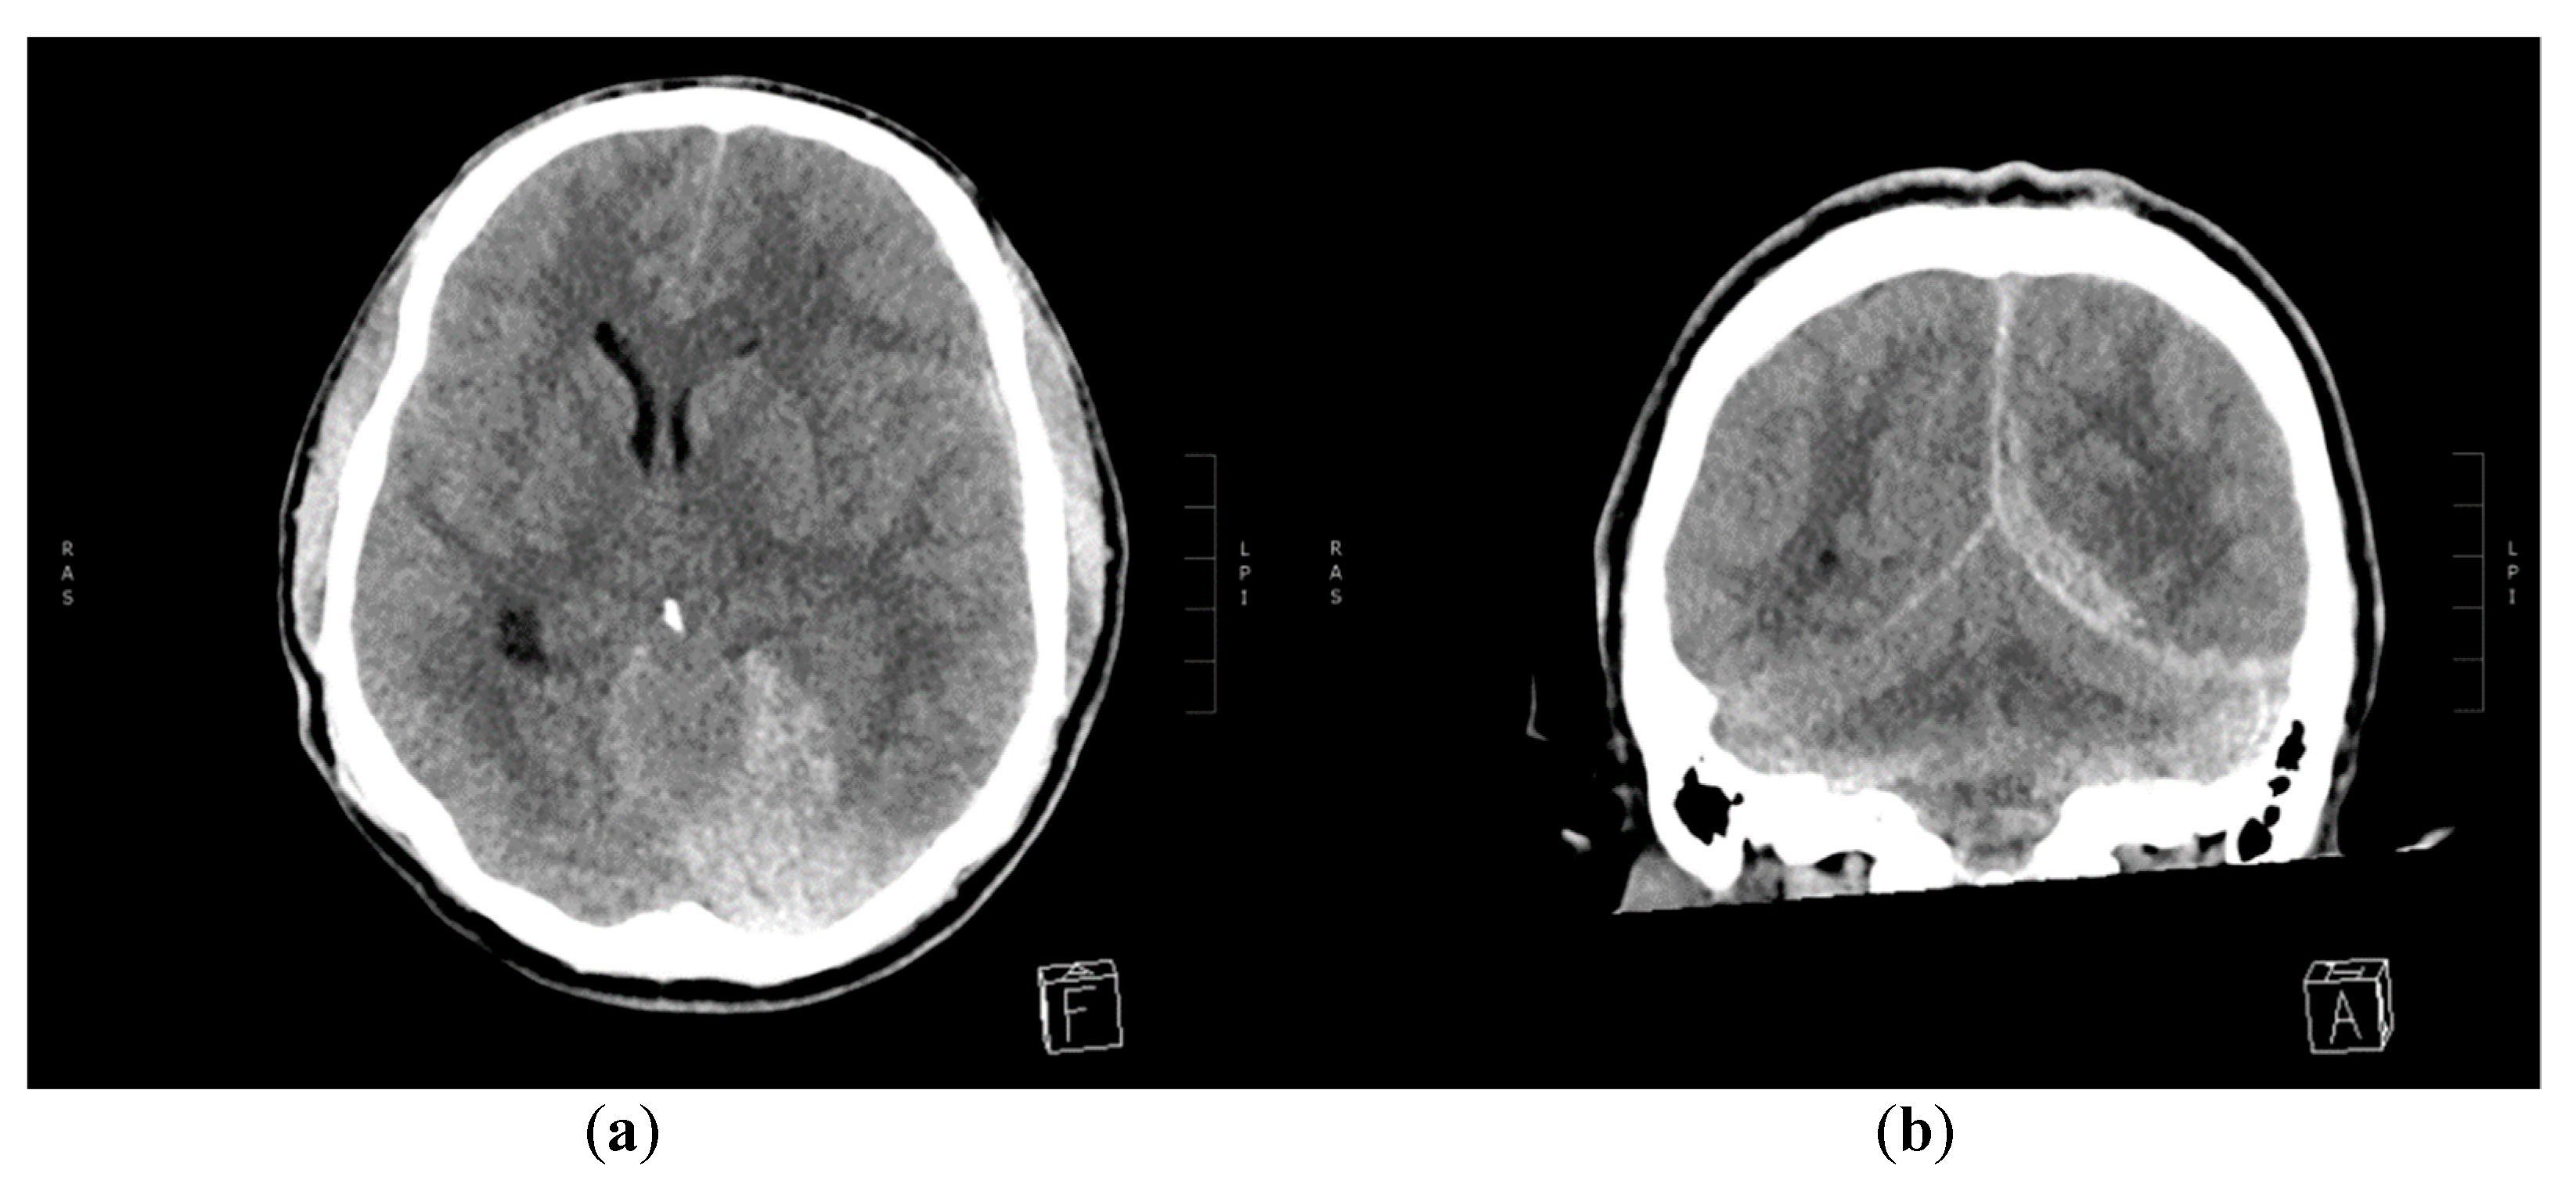

2. Case Report